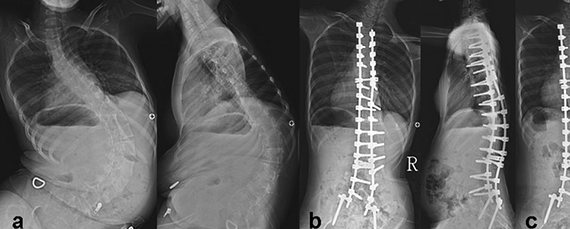

На рентгеновских снимках видно искривление позвоночника и последующее его исправление с помощью операции

Среди возможных методов лечения, используется и хирургическое вмешательство для более радикального воздействия на контрактуру. При СМА, распространенная проблема – сколиоз. Кривизна позвоночника является серьезной проблемой не только для двигательных функций, но и для сердечных и дыхательных систем. Эта ортопедическая проблема имеет активно прогрессирующий характер, и может привести к смертельному исходу.

Возраст начала СМА типа 2 (промежуточным СМА) составляет от семи до 18 месяцев. Симптомы включают слабость в руках, ногах, нижней части туловища и дыхательных мышцах. Искривление позвоночника нередко является проблемой, требующей бодрости и хирургического вмешательства.